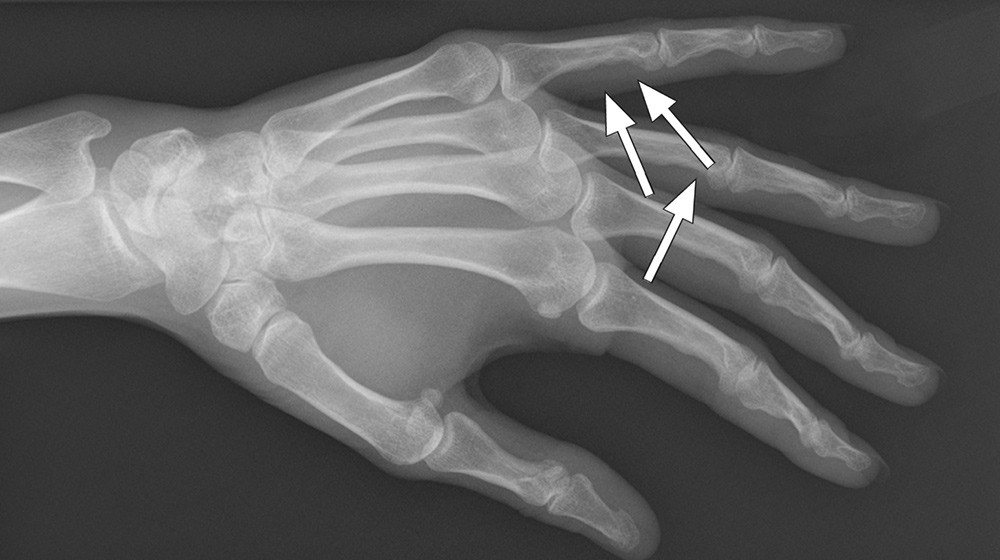

Som ledd i utredning av langvarige smerter i hendene ble det tatt røntgenbilder. Bildene, tatt med skråopptak, viste kortikal utsparing i skjelettet i fjerde og femte grunnfalang (piler). Funn av slik skjelettaffeksjon støttet diagnosen sarkoidose.

Radiologisk skjelettaffeksjon forekommer hos 1 – 13 % av sarkoidosepasientene (2). De vanligste røntgenologiske skjelettforandringene ved sarkoidose er lytiske lesjoner med bølgeform og gitterverksmønster. Skjelettforandringer ved sarkoidose forekommer vanligst i hender, og patologiske frakturer kan forekomme (3).